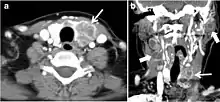

Fig. 10. Metastatic squamous cell carcinoma of unknown origin in a 42-year-old female patient. a, b Axial and coronal enhanced neck CT scan demonstrate infiltrative hypodense left thyroid lobe lesions (white arrows). There are multiple necrotic cervical nodal metastases (white block arrows).[1]

Metastasis to the thyroid is rare and represents 5.5% of biopsied thyroid malignancies. It is commonly found with cancers originating from the breast, renal cell, lung, melanoma, and colon. Direct invasion from adjacent structures such as the pharynx, larynx, trachea, or oesophagus has been reported (Fig. 10). Metastatic disease has a non-specific appearance.[1]